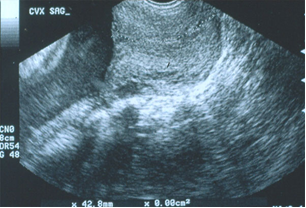

- Siêu âm bìu:

- Các bất thường của tinh hoàn như: nang mào tinh, tràn dịch tinh mạc, giãn tĩnh mạch thừng tinh, sỏi nhỏ tinh hoàn.

Đặc điểm siêu âm bìu

Bảng 4. Các đặc điểm siêu âm bìu

Trong các bất thường ở bìu được phát hiện qua siêu âm, giãn tĩnh mạch thừng tinh chiếm tỉ lệ cao nhất: 36,4%.